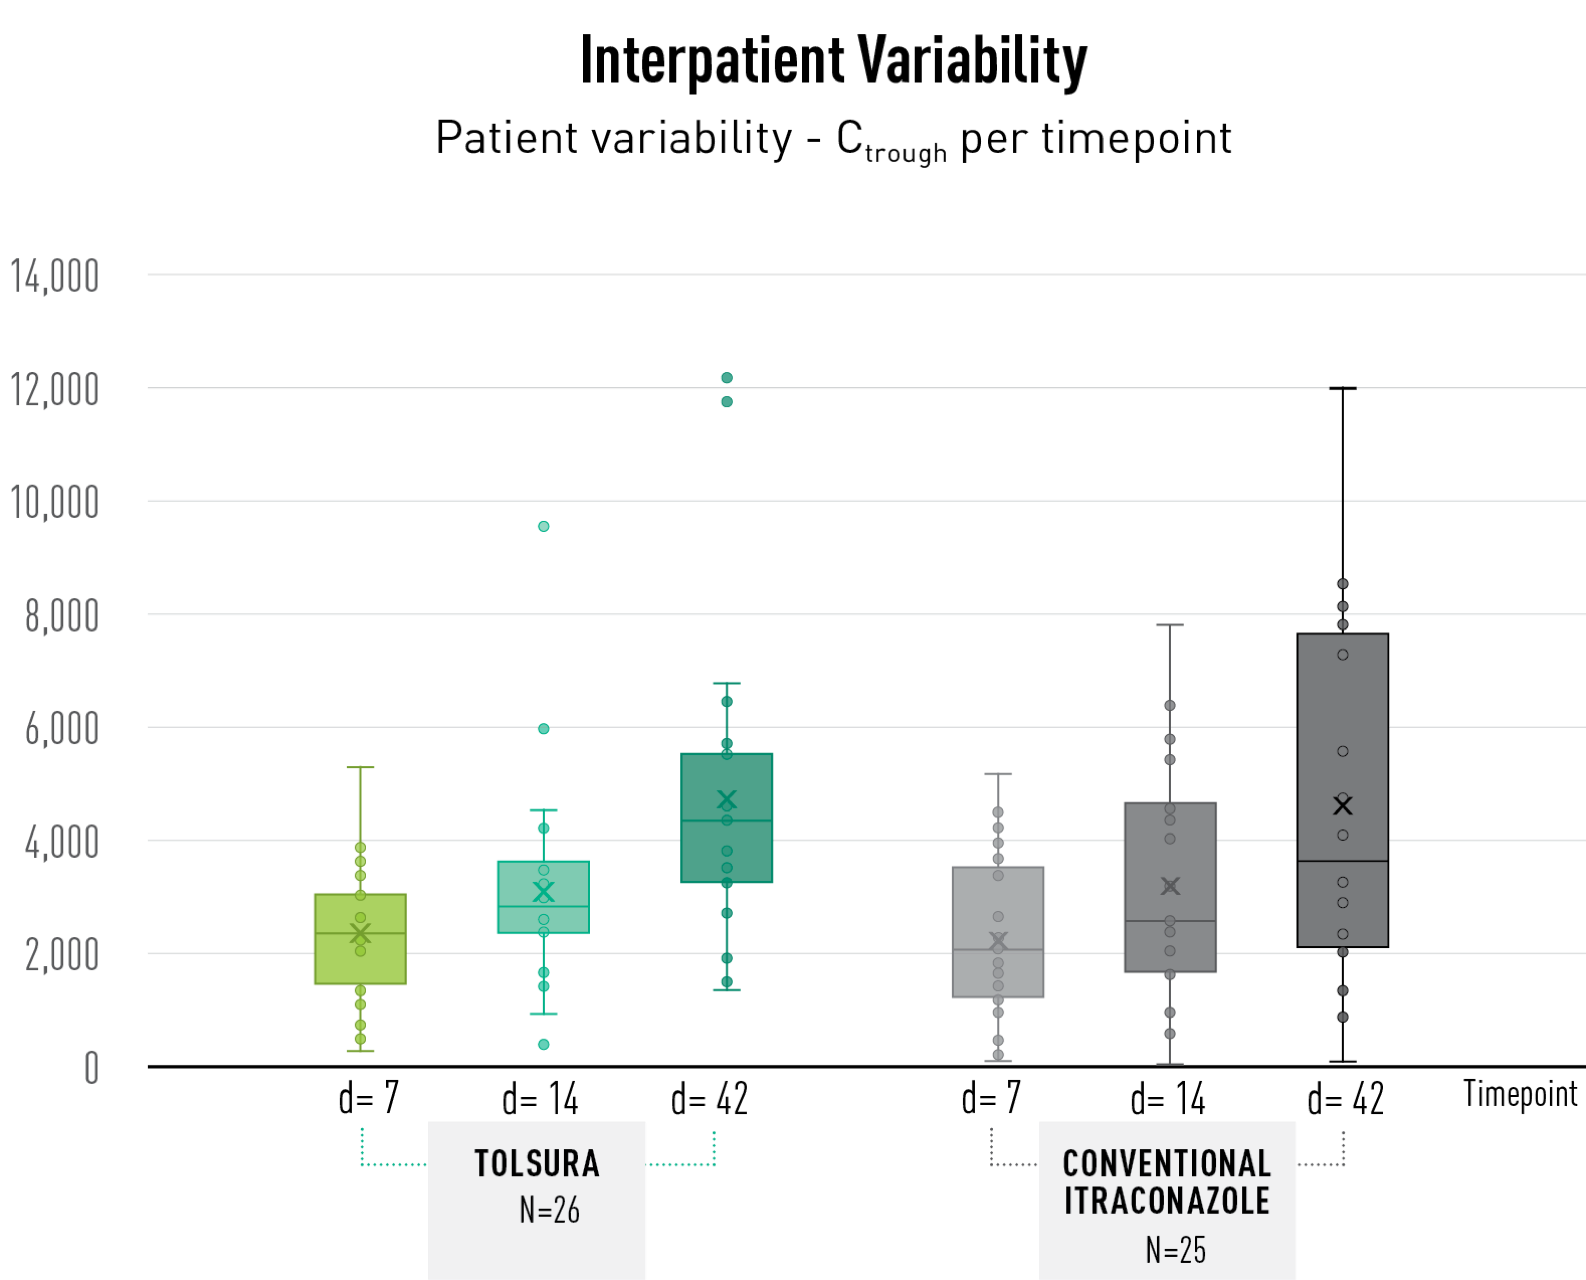

TOLSURA SHOWS LESS PATIENT VARIABILITY than conventional itraconazole1 (Figure)

- N=2 patients with high exposure in the TOLSURA group received dose reductions

10% of conventional itraconazole patients had not achieved therapeutic levels of itraconazole by Day 42; 100% of TOLSURA patients were above the therapeutic threshold3

To date, pharmacokinetic data is available through Day 42 of treatment (N=51; histoplasmosis or blastomycosis patients). Blood serum levels of itraconazole and hydroxyitraconazole were measured on Days 7, 14 and 42 and plotted to compare the variability among patients. All patients in both treatment arms were initiated with a loading dose. As expected, dosing adjustments were needed in some patients especially at the start of therapy.

At each timepoint, and by day 42, interpatient variability is less with TOLSURA than with conventional itraconazole.